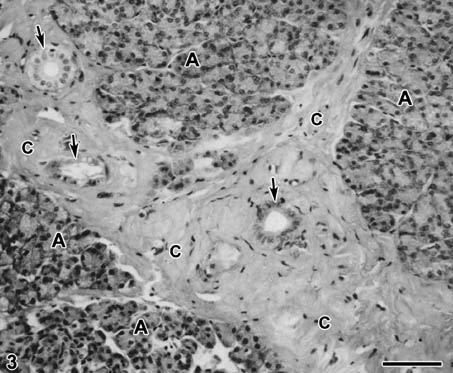

Orchiectomized rats displayed no difference in morphology of the parotid tissue until day 8 of the study. In groups of rats sacrificed after 8-60 days of the experiment, a gradual increase in the interacinar and interlobular connective tissue could be noted (Figs. 2, 3). Because of the increased presence of the connective tissue, the acini of orchiectomized animals seemed to be less represented in the section. However, no significant changes with regard to the morphology of the acinar tissue itself, as well as to the structure of the duct system between the orchiectomized and control rats, could be observed (Figs 2, 3).

Fig. 3. Orchiectomized rat after 60 days of the experiment. Within the augmented connective tissue (c), interlobular ducts (arrows) are situated. The acini (A) of the neighbouring lobules seem to be less abundant. ×200, Bar=100 µm.